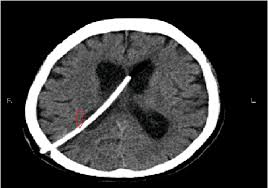

Acute Hydrocephalus From Vp Shunt Blockage Radiology Case Radiopaedia Org